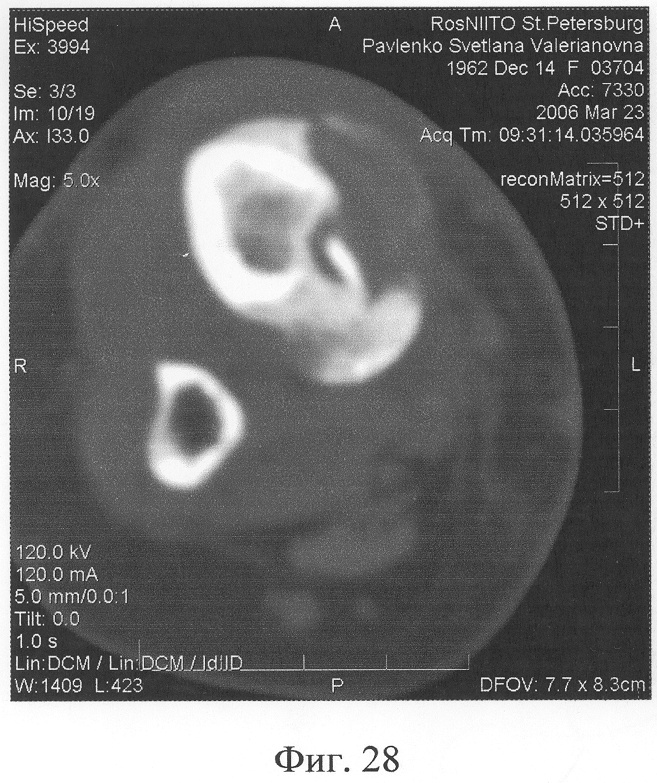

Аппарат внешней фиксации с левой голени демонтирован через 3 месяца после операции при клинико-рентгенологической картине сращения перелома. Аппарат внешней фиксации с правой голени демонтирован через 7 месяцев после операции при клинико-рентгенологической картине сращения перелома (фиг.20-25 – результат лечения). При рентгенологическом и томографическом контроле в трансплантатах отмечалось постепенное нарастание плотности костной ткани с формированием костной мозоли на всем протяжении между трансплантатом и костными фрагментами (фиг.26-29 – динамика данных компьютерной томографии правой голени: отмечается нарастание плотности костной ткани в области трансплантатов и формирование регенерата между смещенным трансплантатом и костными фрагментами; фиг.30-33 – динамика данных компьютерной томографии левой голени: отмечается нарастание плотности костной ткани в области трансплантатов и формирование регенерата между трансплантатом и костными фрагментами).